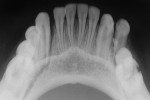

Nineteen patients between the ages 3 and 12 years with maxillofacial injuries (Figure 1 and Figure 2) presented to the Department of Pedodontics and Preventive Dentistry in K D Dental College and Hospital, Mathura, India. Detailed case histories, clinical examinations, and radiographic investigations such as orthopantomography, occlusal radiography, and intraoral periapical radiography were performed (Figure 3 through Figure 8). After careful evaluation, a diagnosis of the type of fracture was made and a treatment plan was formulated for each patient. Informed consent was obtained from the parent, and in some cases, treatment was performed under general anesthesia, with written consent obtained from the parent.

In all patients, splints and arch bars were removed after 2 to 4 weeks. Postoperative radiographs were obtained to confirm the healing of the fractured site before removal of the splint (Figure 5 and Figure 8), and all the patients were followed-up for 12 months. None of the patients had complications in the postoperative period, and uneventful healing and union of the fracture segment occurred in all patients. In one patient, healing time was prolonged because of continuous dislodgement of the splint, which was re-cemented. A slight discrepancy in the occlusion in a few patients was observed, which was corrected on its own over the course of time.